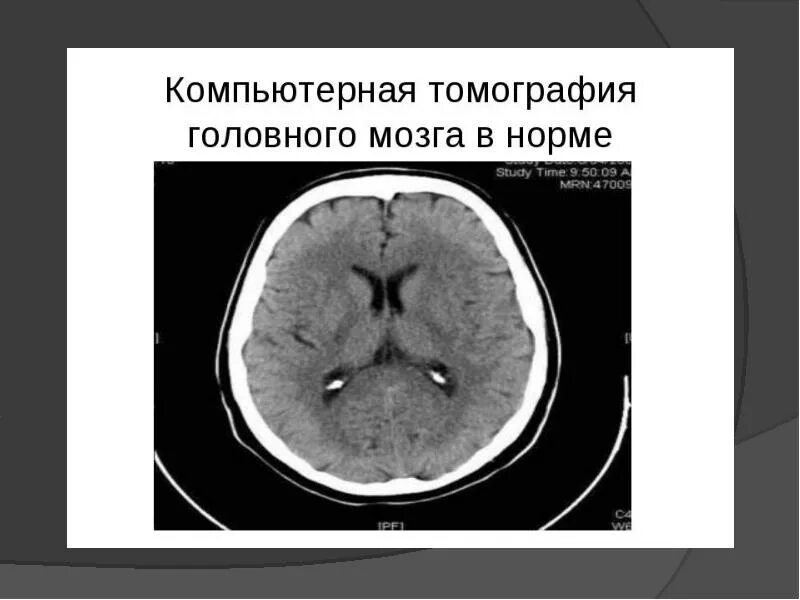

Кт пример